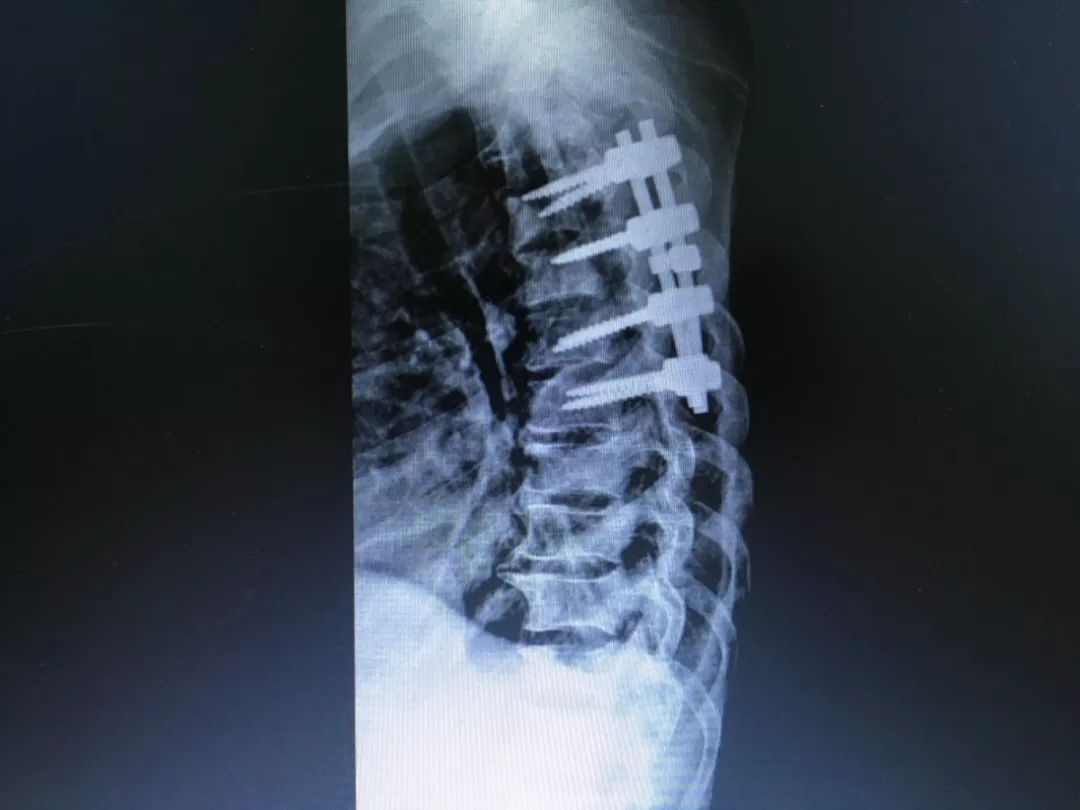

开业至今(9 月底),病患门急诊量增长显著,已完成各类手术总量 2 776 例;成功完成高难度的脊柱、关节等方面的四类手术数量 736 例,如胸椎肿瘤切除手术、全髋关节及全膝关节置换手术、脊柱侧弯矫正手术等,占手术总量近 3 成,让北仑患者在家门口享受到了优质医疗资源,获得了患者的好评。

18岁脊柱侧弯术前

18岁脊柱侧弯术后

胸椎肿瘤术后

左右滑动查看更多